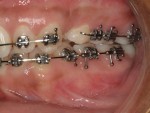

The surgical team spends much time and energy in collaboration with the orthodontist to plan the surgery.  A joint treatment plan is devised.  The orthodontist sets up for the surgery with braces.  The surgical team then plans the surgery using xrays to predict the movements, performs the surgery on models, then fabricates acrylic splints to guide the surgical team in the operating room.

After Orthodontic Setup - Presurgical